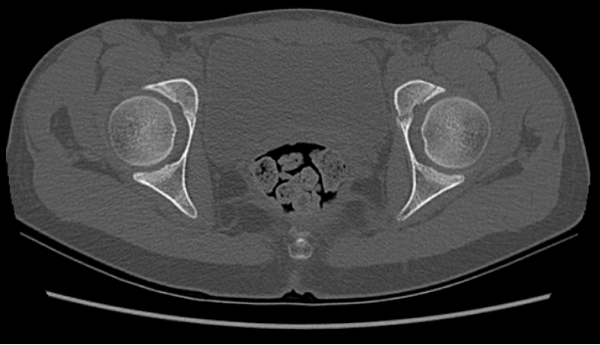

Corte axial en ventana ósea de TC de pelvis (Imagen 8). Asimetría en la rama ilio-pubiana del cartílago trirradiado, con mayor amplitud a izquierda.

Colección hemática entre el periostio y la cortical, generalmente post traumática. Se presenta como una lesión lentiforme adosada al hueso, con niveles líquido-líquido en RM y sin realce significativo tras contraste. Puede asociarse a calcificación periférica en TC. Los hallazgos descritos y el antecedente clínico son concordantes con este diagnóstico.